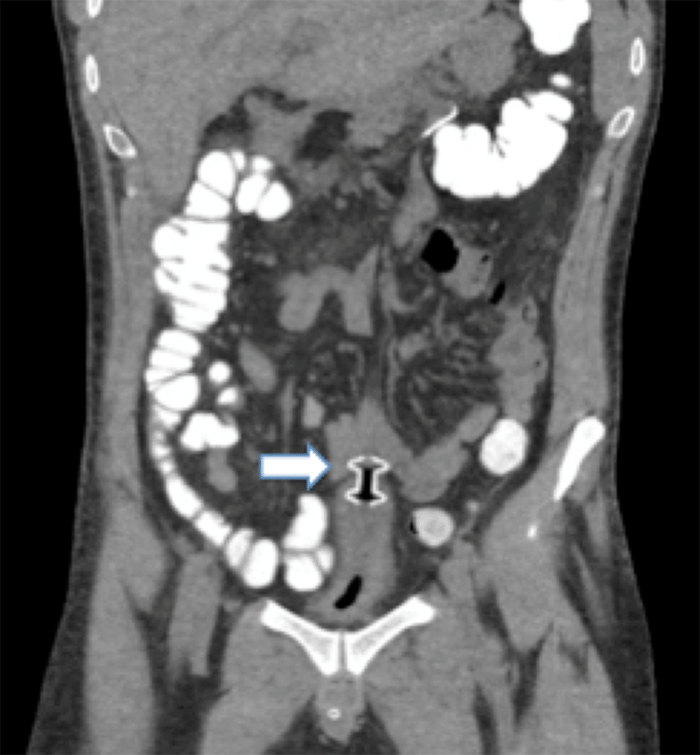

Repeat CT of the abdomen and pelvis with only oral contrast was done and revealed the recently placed Axios™ stent vertically oriented in the pelvis. The cephalad and caudal portions of the stent were noted to communicate with a loop of the small bowel and the urinary bladder dome, respectively (Figure 2).

Figure 2. Coronal CT With Oral Contrast of AxiosTM Stent (arrow) in Pelvis, with Superior Portion Seen Communicating With Small Bowel and Caudal Aspect Involving Bladder Dome. Published with Permission